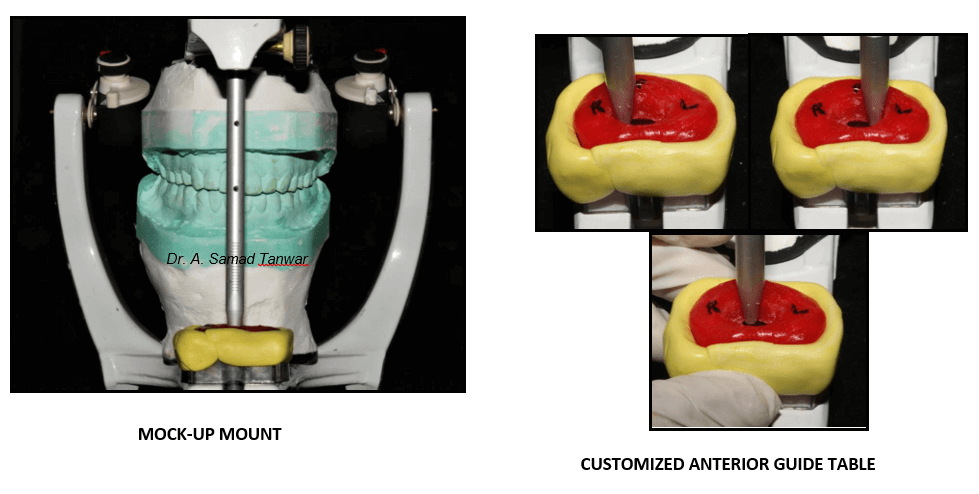

The patient was guided into centric relation and it was mounted on a semi- adjustable

The articulator was programmed using protrusive and lateral interocclusal

Full mouth wax up was done

Impression was made of the adjusted mock-up and then it was mounted on a semi-adjustable

Customized anterior guide table was fabricated using pattern resin performing eccentric movements i.e. protrusive, right lateral and left